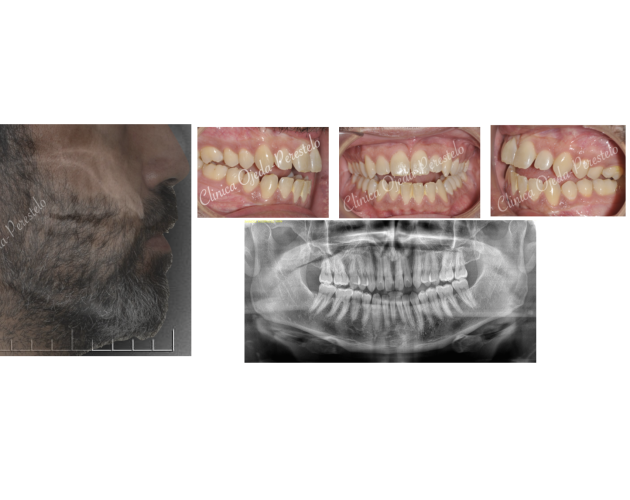

Clase II esquelética con Cirugía de Avance Md Casos de Éxito - Ortodoncia Plástica (Invisalign/Angel) - Adultos

Clase II severa en Mandíbula Hipoplásica Casos de Éxito - Adultos - Cirugía Ortognática

Clase II osea de causa Md con Cara Larga Casos de Éxito - Adultos - Cirugía Ortognática